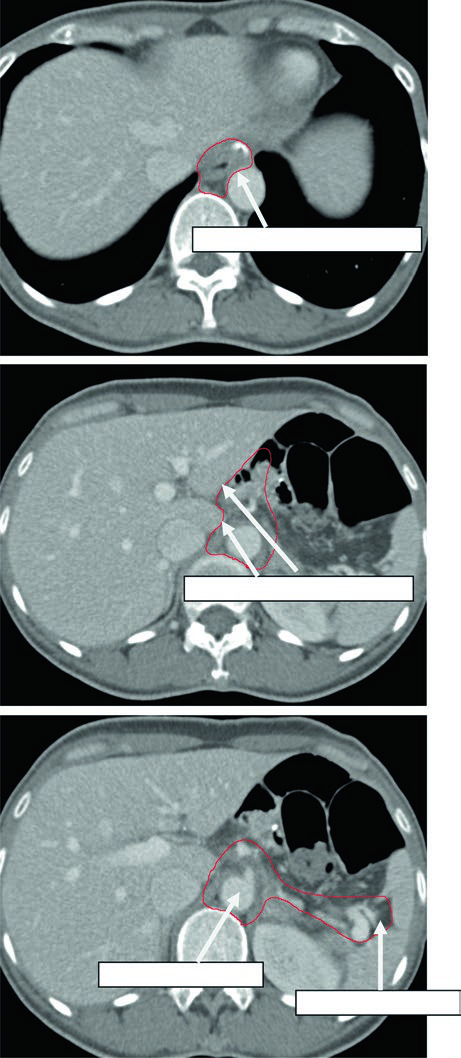

Caso 1: T1N1M0 Adenocarcinoma da Cárdia — Gastrectomia Total

Neste caso, o CTV engloba a anastomose esofagojejunal, o ligamento hepatogástrico, a artéria celíaca e o hilo esplênico. Como se trata de gastrectomia total em tumor da cárdia com linfonodo positivo, não há remanescente gástrico a incluir, mas os volumes nodais devem ser amplos.

Caso 2: T3N3M0 Adenocarcinoma do Corpo — Gastrectomia Distal

Com doença T3N3, o CTV é extenso: inclui anastomose gastrojejunal, estômago remanescente, artéria celíaca, hilo esplênico e leito tumoral pancreático. Esse cenário exige atenção especial às restrições de dose nos órgãos de risco — particularmente rins e fígado — pois o volume de tratamento é considerável.

Caso 3: T2N1M0 Adenocarcinoma de Antro/Piloro — Gastrectomia Distal

No adenocarcinoma de antro/piloro, o CTV abrange a anastomose gastrojejunal, o estômago remanescente, o ligamento hepatogástrico e o coto duodenal. A cobertura do hilo esplênico é opcional neste cenário. A inclusão do coto duodenal é preferencial em gastrectomias parciais por tumores distais/antrais, mas não deve ser incluída em pacientes com tumores proximais submetidos a gastrectomia total.